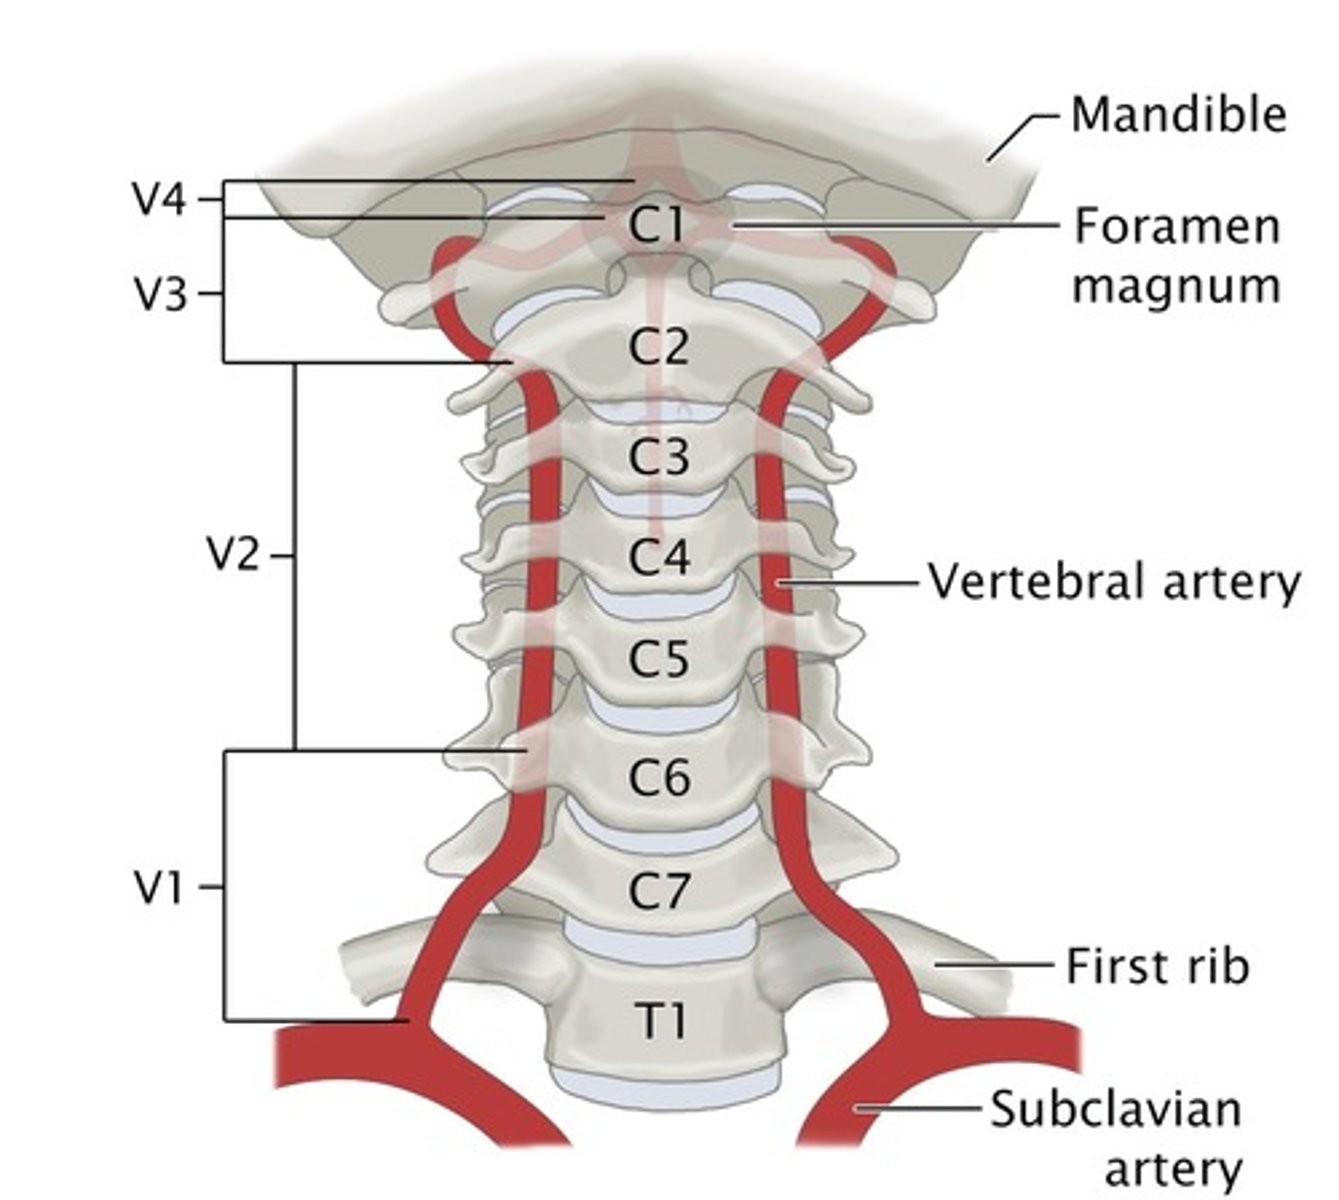

Arteries that ascend the vertebrae, enter the base of the skull, and join together to form the basilar artery.

vertebral arteries (articulated vertebral column)

Where does the vertebral artery enter so that it can continue on to the brain?

transverse foramen in vertebrae